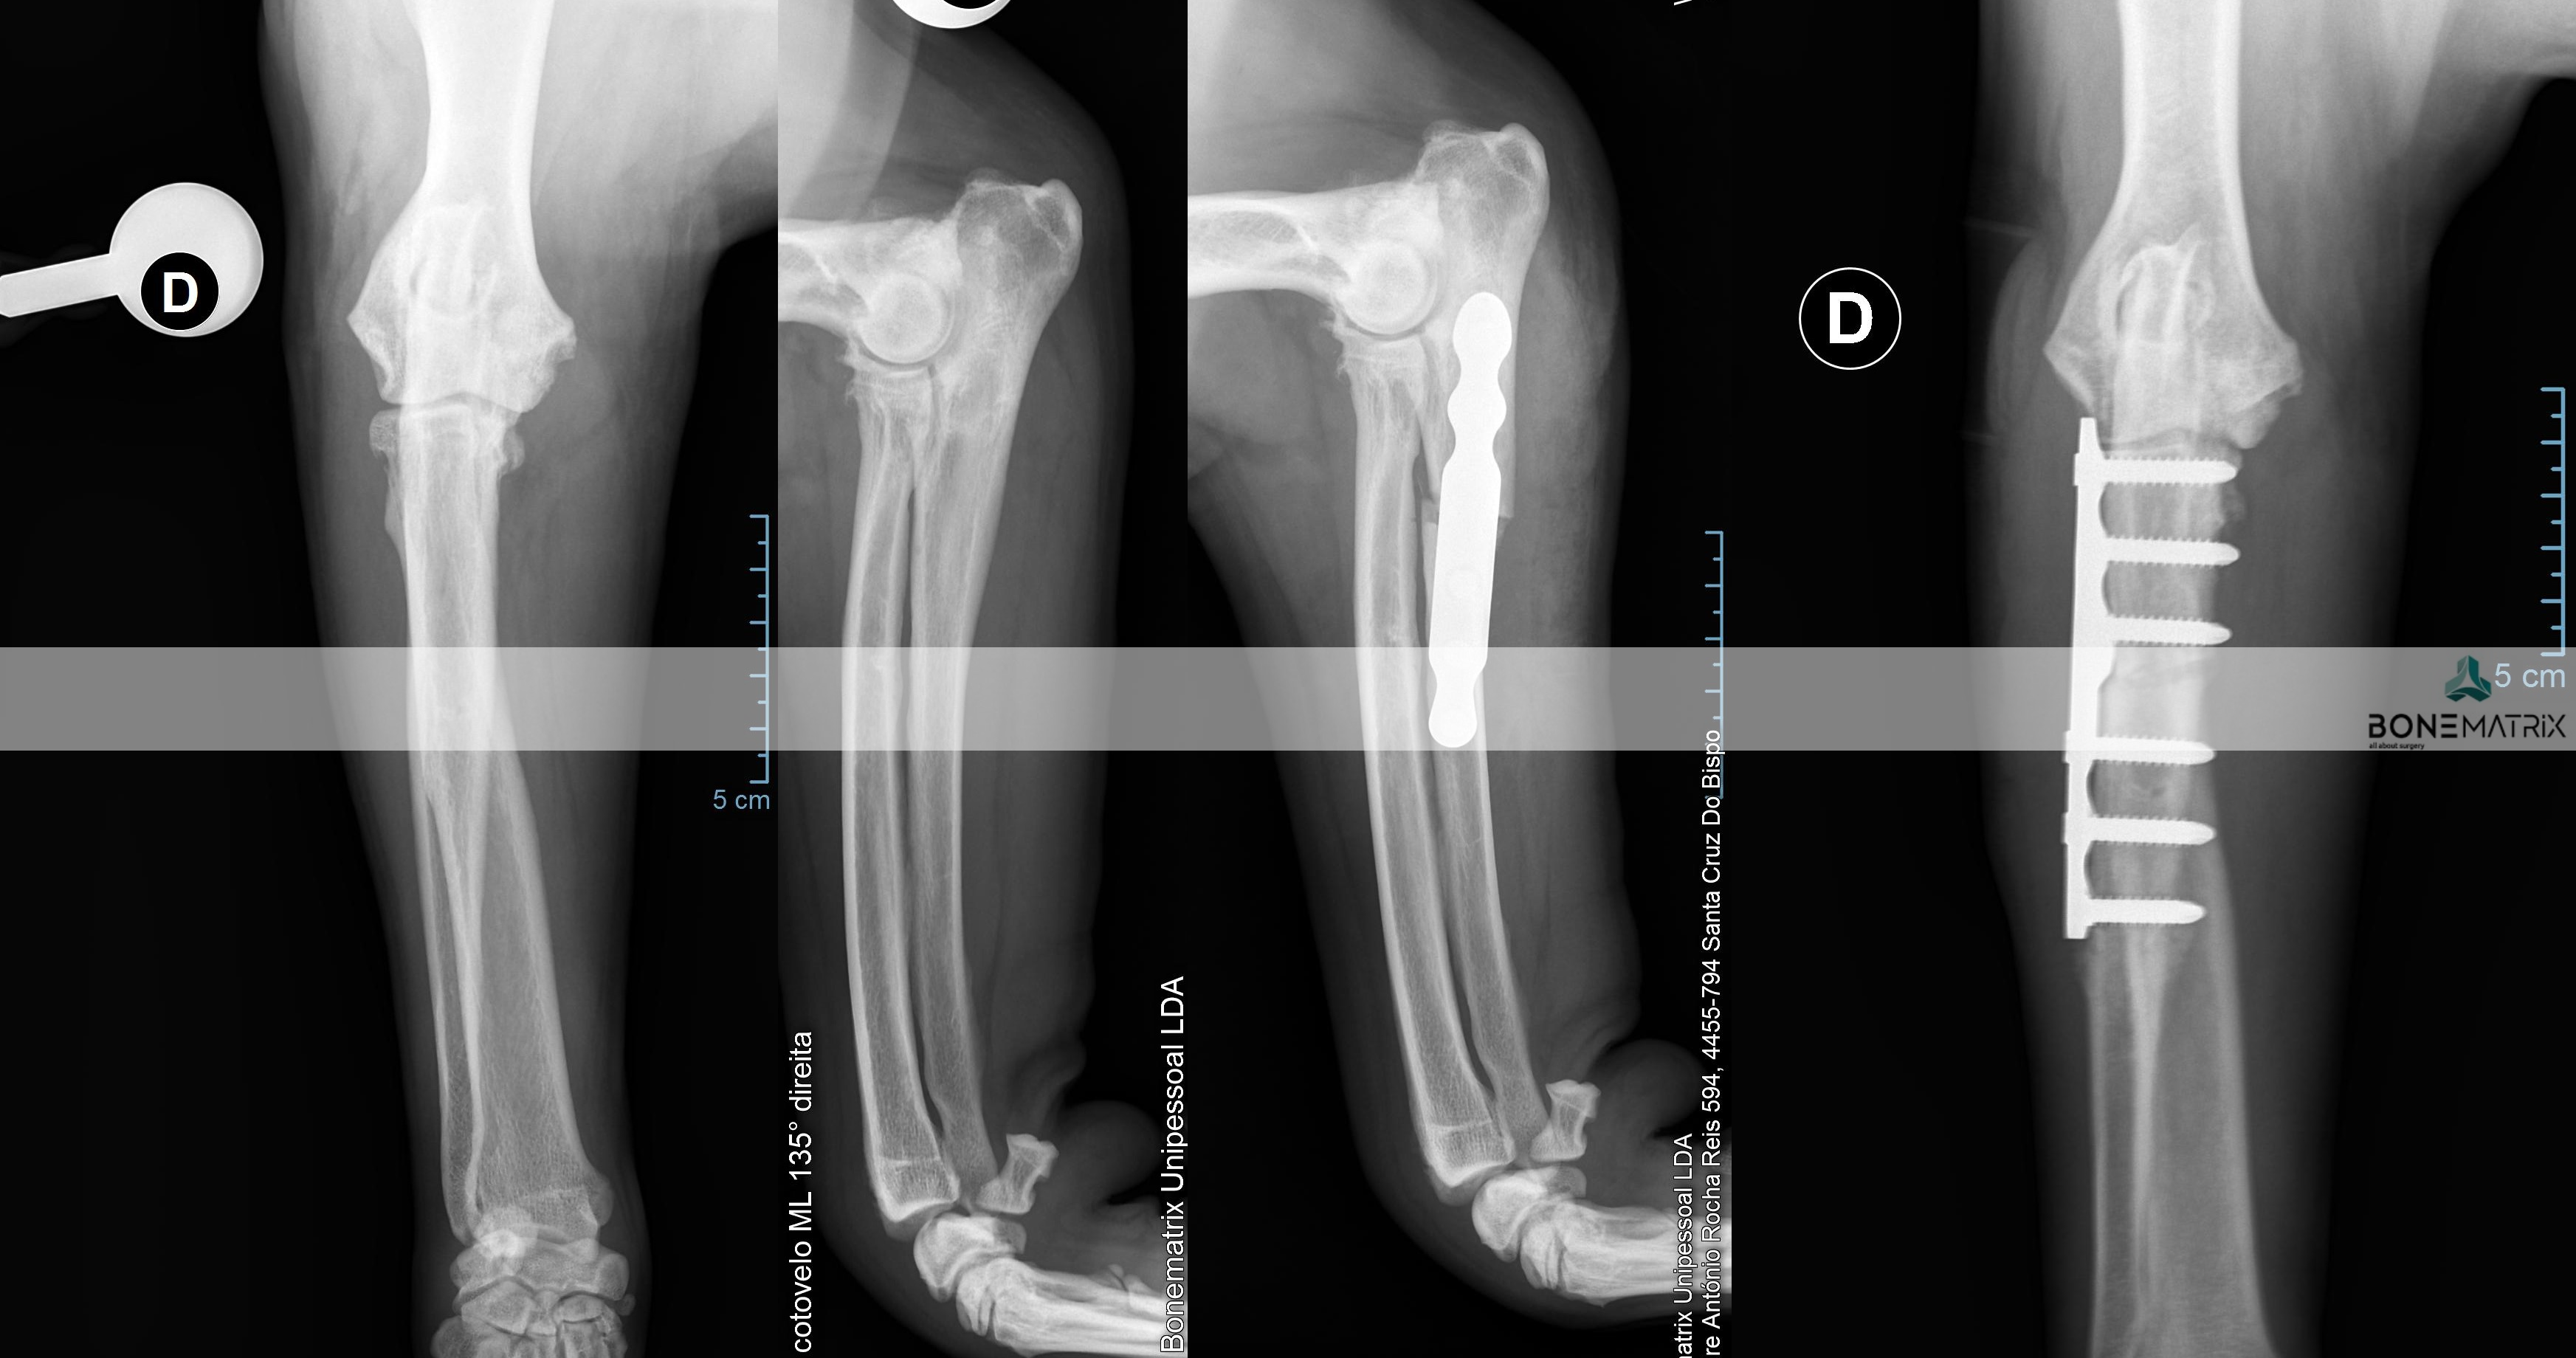

A displasia de cotovelo é uma doença de desenvolvimento caracterizada pela incongruência do cotovelo.

Dada a componente genética, frequentemente envolvida no decorrer deste processo, a patologia apresenta-se por norma bilateralmente, podendo assumir gravidade diferente em ambos os cotovelos.

Esta patologia quando unilateral, por norma, está relacionada com um evento traumático, ocorrido durante o crescimento do animal.

A displasia de cotovelo pode assumir várias apresentações, entre elas, a não união do processo ancóneo, a fragmentação do processo coronóide, a osteocondrite dissecante, doença do compartimento medial e a incongruência per si.

Todas estas apresentações tem em comum contribuírem para o desenvolvimento acelerado de um quadro de osteoartrite a nível intra-articular.

Como é criada esta incongruência?

A articulação do cotovelo é constituída por 3 ossos, o rádio, a ulna e o úmero.

A incongruência do rádio resulta na apresentação deste osso mais curto que a ulna. Isto resulta num excesso de pressão sobre regiões da ulna - resulta com frequência na fragmentação do processo coronóide.

Quando a apresentação contrária ocorre, ou seja, o rádio apresenta-se mais elevado que a ulna, é exercida demasiada pressão sobre o processo ancóneo - resultando com frequência na não união do processo ancóneo.

Quando a incongruência envolve o úmero outras lesões podem ser desenvolvidas que envolvem o desalinhamento articular entre o úmero e a ulna.

As incongruências descritas também podem ser consequência de um encerramento precoce traumático das placas de crescimento destes ossos (locais responsáveis pelo crescimento longitudinal dos ossos).

A apresentação desta patologia em fases iniciais apresenta, com frequência, sinais subtis, daí a necessidade de realização de despiste de displasia de anca durante o crescimento do animal (idealmente 5 meses) para que a doença possa ser detetada antes que ocorra um desenvolvimento significativo de lesões de osteoartrite a nível intra-articular.

O diagnóstico pode ser realizado por meio de estudo radiográfico.

Contudo são indicadas técnicas de imagem avançada (tomografia axial computorizada) ou artroscopia para a realização do diagnóstico final e definição de abordagem terapêutica.

Qual o tratamento indicado?

O tratamento depende da forma de apresentação da doença a nível articular.

Vários são os procedimentos terapêuticos que podem ser feitos com recurso a artroscopia, nomeadamente desbridamento de lesões cartilagíneas, remoção de fragmentos do processo coronóide, remoção sub-total do processo coronóide, assim como também é possível a remoção de flaps de lesões de osteocondrite dissecante.

A resolução da incongruência articular é realizada por meio de um corte corretivo realizada na ulna. Este corte vai permitir que este osso se readapte à articulação de forma a que todas as estruturas constituintes da articulação suportem o peso de uma forma equilibrada, sem sobrecarregar nenhuma região. A cirurgia realizada com maior frequência neste sentido designa-se por PLUS.

Esta técnica é maioritariamente aplicada em patologia de displasia de cotovelo.

A displasia do cotovelo apresenta várias formas, sendo que todas as apresentações têm em comum a existência de um crescimento assíncrono dos ossos constituintes da articulação.

Este crescimento assíncrono faz com que a ulna, o rádio ou o úmero não estejam perfeitamente posicionados dentro do espaço articular (incongruência articular). Esta incongruência resulta no sobrecarregamento de determinadas zonas dentro do cotovelo. O sobrecarregamento destas zonas provocam o desenvolvimento de lesões na cartilagem.

As lesões cartilagíneas, por si só assim como também por conduzirem ao desenvolvimento de quadros de osteoartrite, podem levar a processos de dor e desconforto bastante debilitantes para o animal.

Inicialmente deve ser realizado um despiste de displasia de cotovelo com recurso a um estudo radiográfico específico para que o paciente seja avaliado e seja definido como um bom candidato à aplicação desta técnica.

O que é a PLUS?

A PLUS (Petazzoni longitudinal ulnar slidding) é uma cirurgia realizada com o intuito de recuperação de congruência a nível articular, no cotovelo.

Esta cirurgia consiste na realização de um corte com características especificas na ulna que permite a sua movimentação deste osso e reajuste da sua posição dentro da articulação do cotovelo.